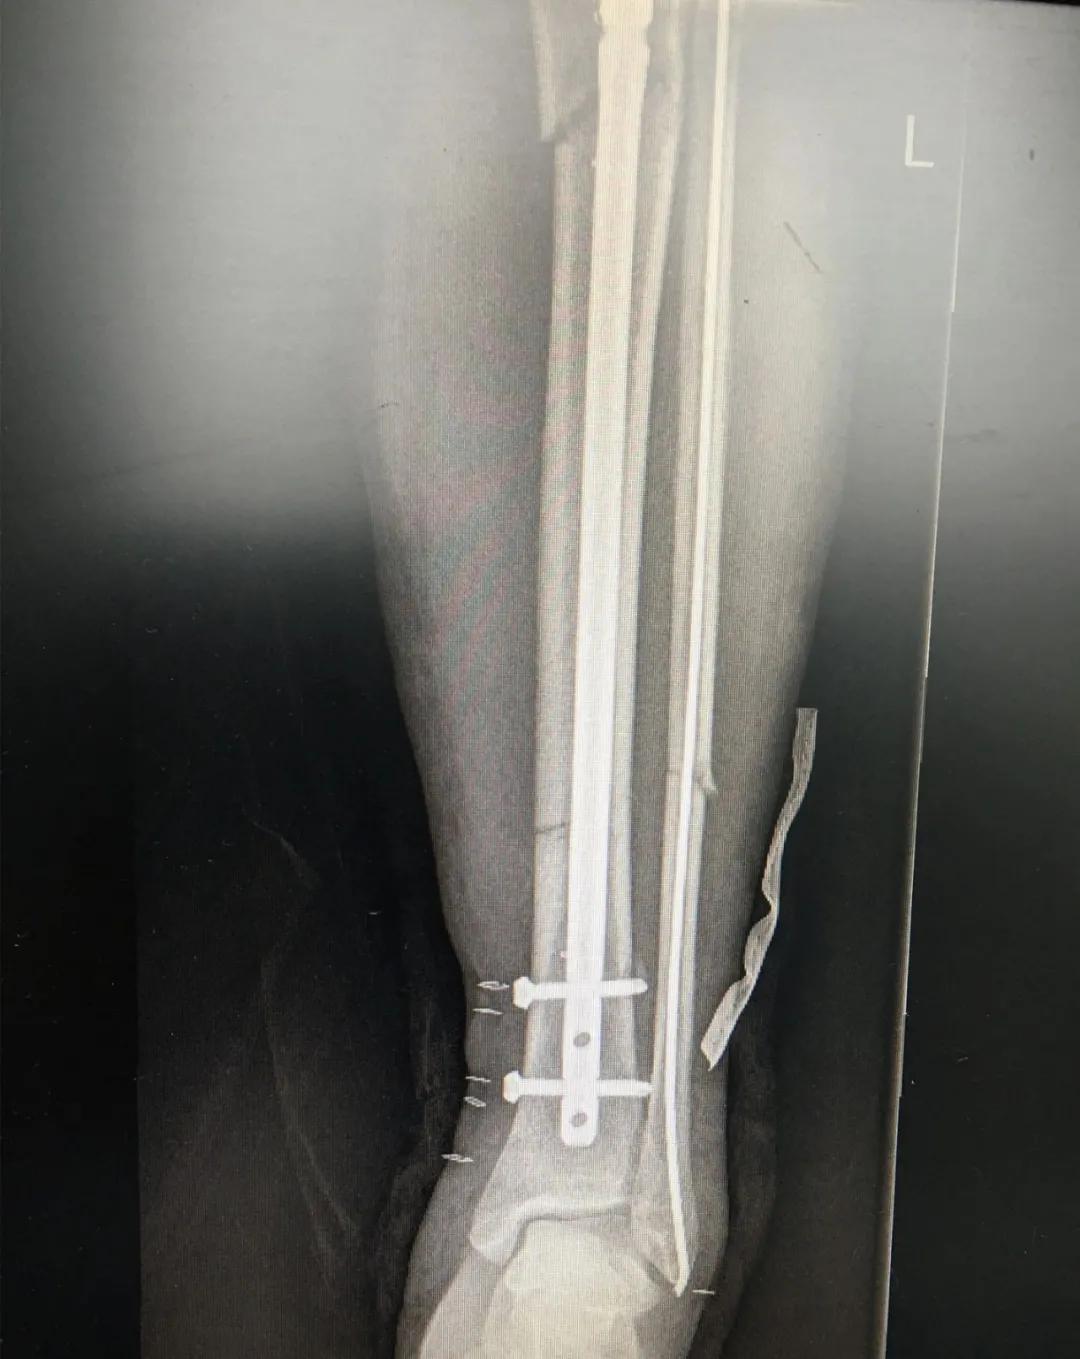

刘阿姨半个月前骑电动车时与小轿车相撞,导致了左胫腓骨粉碎性骨折,小腿骨碎成了三段。"然而,在术前丈夫周先生对刘阿姨的治疗却拿不定主意。“我妻子身上有多种基础疾病,患高血压15年,糖尿病也有8年多了。这里的诊疗技术,能不能保障手术的安全?手术前,我们家属的心中确实也很忐忑!"由于对我院创伤技术水平不太了解,周先生已经准备要转院治疗。

为患者实施的骨折微创复位固定技术是创伤骨科的特色技术。相较传统手术需要20公分的切口,微创手术只需要3公分左右。闭合复位髓内钉固定技术、经皮插板内固定技术(mippo技术)、闭合复位空心螺钉固定技术等一系列的微创复位固定技术,具有切口小、出血少、创伤小、愈合快、疤痕小等优点,骨折术后并发症明显降低,患者还可以早期负重功能锻炼。

另一位患者朱先生因车祸导致了右胫腓骨骨折,同样的小腿三段骨折,实施了微创闭合复位髓内钉固定术后,目前已经逐步进行康复功能锻炼。